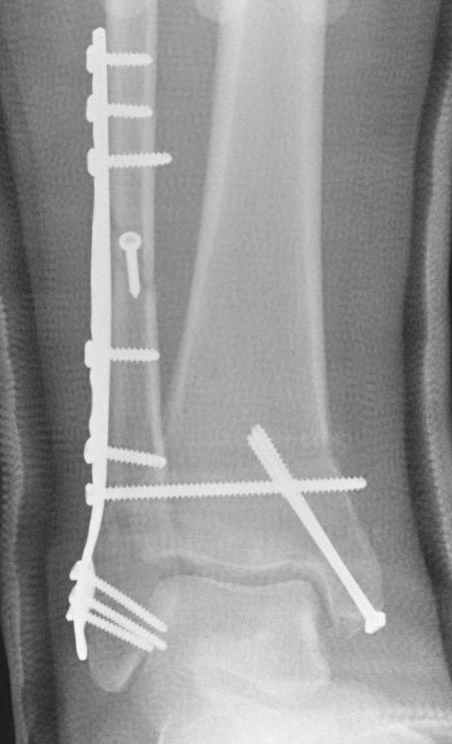

Ниже рентгенограммы

12 января прямой

12 января боковой

12 января трехчетвертной

Риторический вопрос - в каком руководстве рекомендован такой способ остеосинтеза наружной лодыжки?

Очевидно, такой результат операции был запрограммирован. При невосстановленной длине и практически нефиксированной малоберцовой кости (этот кортикальный винт - как карандаш в стакане), при неустраненном подвывихе, невправленной и тоже нефиксированной внутренней лодыжке нет стабильной вилки сустава. Если такую операцию сделать даже сразу, а не через 4 месяца, то результат ожидаем

тот же.

Вариант с артродезом уже обсудили. Хотя, после увиденых снимков, пессимизм насчет восстановительной операции у меня, например, несколько уменьшился. Особенного уж какого-то остеопороза не видно даже на январских снимках. Можно черед мини-доступы убрать винты, аппаратом вправить малоберцовую кость, устранить подвывих стопы. Ну а дальше фиксировать малоберцовую пластиной сзади. А может, и напряженной Y-спицей попробовать - Анатолий Федорович, как Вы полагаете? Внутреннюю - то, что осталось, если уже не получится сделать спицами и проволокой, то что-то типа пластики дельтовидной связки. А может, и не трогать ее вовсе... В общем, выбор непростой,

Если до сих ничего не сделано, с артродезом сустава в данный момент я бы повременил, на выставленных январских снимках хорошо сохранившийся сустав, а в "мортиз" (трехчетвертной) и на боковых снимках не менее 5 мм укорочение малоберцовой кости. Косые переломы лучше фиксировать пластинами, как то мы разбирали случай, где было отмечено, что это закон "таранная кость всегда следует за малоберцовой".

Недавний случай, больной 56 лет получил политравму в Англии, после переведен в США, где его успешно лечил местный ортопед, огромная статья в газете об успешной операции, своеобразный пиар, из-за того, что больной был американский пожарник на пенсии, и за его переезд было заплачено международным пожарным союзом, короче по другим показаниям перевели больного в наш университетский госпиталь.

После 5-6 недели после травмы сделана повторная операция, обошлись без удлинения малоберцовой.

С подобным случаем приходилось сталкиваться у гормонозависимого пациента с 4 месячным подобным переломом после безуспешного лечения в аппарате Илизарова. Вальгусная стопа, остеопороз, диастаз в медиальной лодыжке. Произвел открытую репозицию мед лодыжки, синтез тяговым винтом 3.5 мм из титана, костную пластику спонгиозой, до 2 см куб из надлодыжечной зоны. Затем остеотомия по линии перелома малоберцовой кости узким долотом из 0.5 см доступа и ручная коррекция вальгуса . Блокирующий винт через обе кости. Остеосинтез по MIPO технологии пластиной 1-3 трубки. Внешней фиксации не применялось, перелом сросся за три месяца. Согласен с д-ром Кульжановым, без пластины в подобных случаях не обойтись.